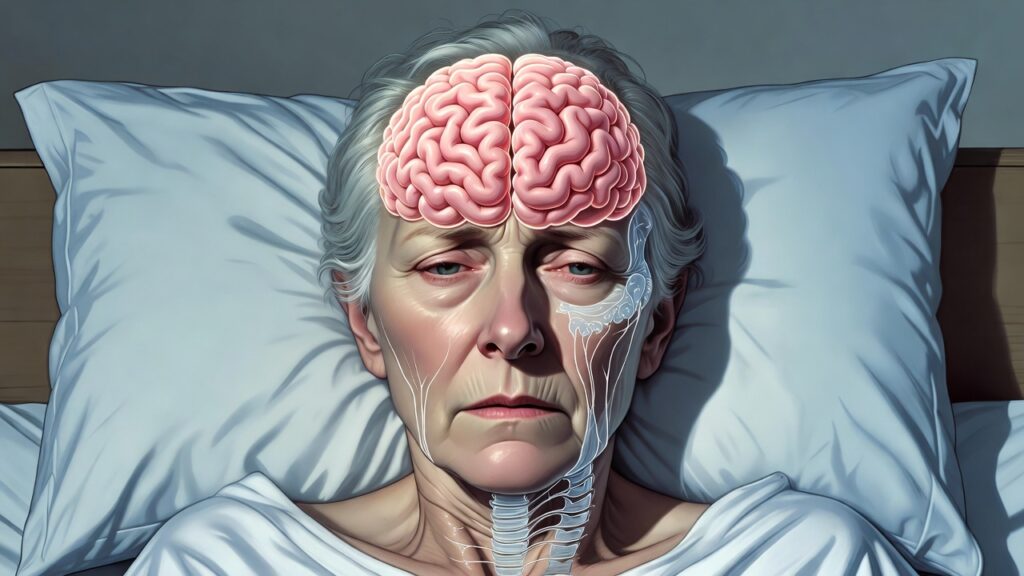

Nipah virus originates in animals and can be passed to humans through direct or indirect contact. It is classified under the Paramyxoviridae family and belongs to the Henipavirus genus, which also includes the equally lethal Hendra virus. Unlike many common viral infections, Nipah virus demonstrates a strong tendency to attack both the central nervous system and the respiratory system. This often leads to acute brain inflammation (encephalitis), serious breathing difficulties, and a high risk of mortality.

- Acute encephalitis

The Nipah virus is particularly troubling from a neurological and psychiatric point of view. In my clinical perspective, patients may exhibit:

• Acute delirium and confusion

• Behavior deprivation

• Anxiety and agitation

• Hallucinations

• Personality development

These symptoms emphasize the virus’s direct brain involvement and emphasize the need for multidisciplinary care.

Neurological Sequelae in Survivors

Survivors may suffer from long-term complications, including:

- Persistent cognitive impairment

- Memory deficits

- Speech and motor difficulties

- Seizure disorders

- Chronic fatigue